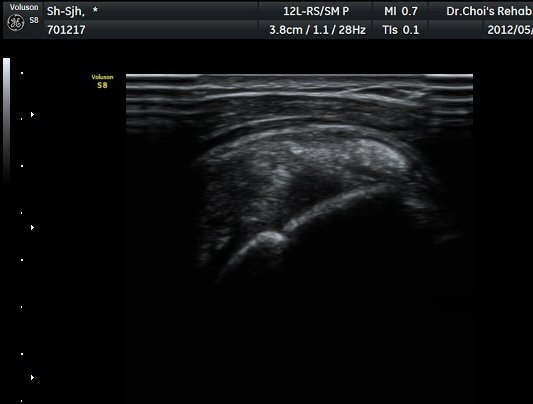

Á߸³»óÅ ¾î±ú ¾Õ Ⱦ´Ü¸é°Ë»ç¿¡¼­ À̺ειڱ٠ÁÖÀ§¿¡ ¼ö¾×Àú·ù°¡ °üÂûµÇ°í(»çÁø 1) ÆÄ¿öµµÇ÷¯

°Ë»ç¿¡¼­ Ç÷·ùÁõ°¡°¡ °üÂûµÈ´Ù(»çÁø 2). À̵ιڱ٠Á¾´Ü¸é°Ë»ç¿¡¼­µµ °Ç ÁÖÀ§ ¼ö¾×Àú·ù°¡ È®ÀÎ